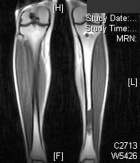

C.G. – 21 year old white female college lacrosse player with four month history of left shin pain worsened by activity. Physical exam demonstrates TTP overlying distal left tibia, extremity NVI.

Zoom image: Radiological image Radiological image.